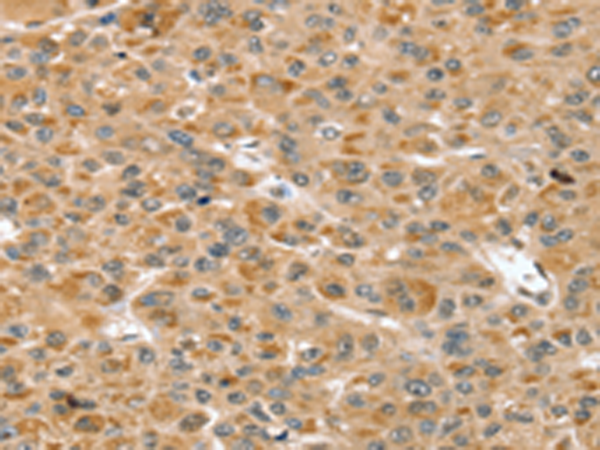

分类: 科研抗体货号: P08713别名: GRAIL应用: IHC反应种属: Human, Mouse